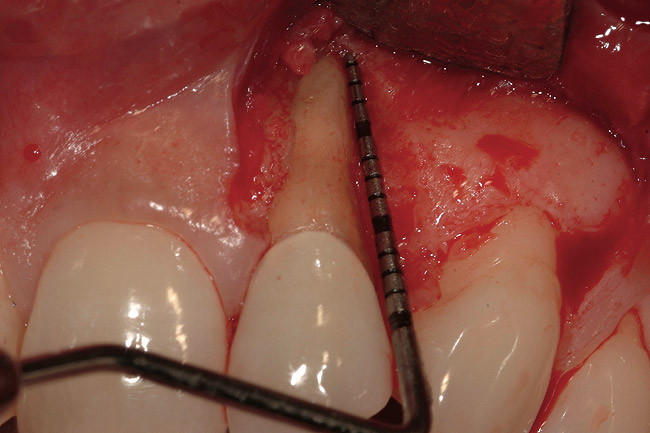

A 34-year-old woman presented with a chief complaint of mild discomfort and swelling associated with the maxillary left lateral incisor. The patient reported a history of root canal therapy and crown performed approximately 10 years earlier. Findings from the clinical examination revealed a localized buccal gingival swelling at the level of the mucogingival junction distal to the lateral incisor, with a 9-mm probing depth on the direct facial of the tooth (Figure 1 ). Observations from the radiographic examination demonstrated a periradicular radiolucency but suggested normal interdental bone levels (Figure 2 ). Surgical exposure following flap elevation exposed a 10-mm dehiscence defect of the buccal plate (Figure 3 ), which was consistent with a vertical root fracture and hopeless prognosis. The lateral incisor was extracted to minimize the loss of alveolar bone and this was followed by thorough degranulation of the socket. Particulate FDBA saturated with rhPDGF-BB for 10 minutes was then applied to augment the deficient ridge in preparation for future implant placement (Figure 4 ). The extraction site was developed to approximate the contours of the adjacent alveolar ridge. Then, a resorbable collagen membrane (Bio-Gide®, Osteohealth) was placed over the graft to facilitate graft containment and maintenance of desired alveolar contours (Figure 5 ). Placement of the membrane without disruption or displacement of the graft during completion of the surgical procedure and suturing is critical to ensure clot formation that will support bone formation.

Figure 3  Surgical flap elevation reveals a 10-mm facial bony dehiscence.

Figure 3

Figure 14  Periapical radiograph of fractured maxillary left canine with a calibrated point (15-mm markings) demonstrating extent of attachment loss on mesiobuccal aspect of the tooth. Similar probing was present on the distobuccal aspect of the tooth.

Figure 14